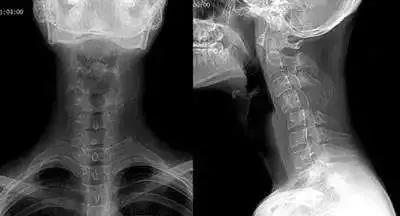

低头族越来越多,颈椎问题也随之而来。近年来,门诊中经常遇到因颈部疼痛不适前来就诊的年轻患者,拍颈椎X片后,影像学报告往往显示“颈椎曲度变直”。这个听起来有些陌生的医学术语,实际上反映了现代人普遍面临的健康隐患。

颈椎生理弯曲是指正常情况下颈椎向前凸出20-25°的弧度。这个弧度的存在并非偶然,而是人体进化的结果。它不仅能保持站立、行走时目视前方,还能吸收震荡,保护头部和脊髓。颈椎曲度的维持主要依靠椎间盘的弹性以及颈椎前后方肌肉和韧带的良好张力。

然而,现代生活方式正在悄然改变我们的颈椎。长期低头、睡姿不良等因素导致颈椎间盘髓核脱水、退变,颈椎前凸逐渐消失,甚至变直或反弓。这种变化不仅影响美观,更重要的是会对身体健康造成诸多不利影响。